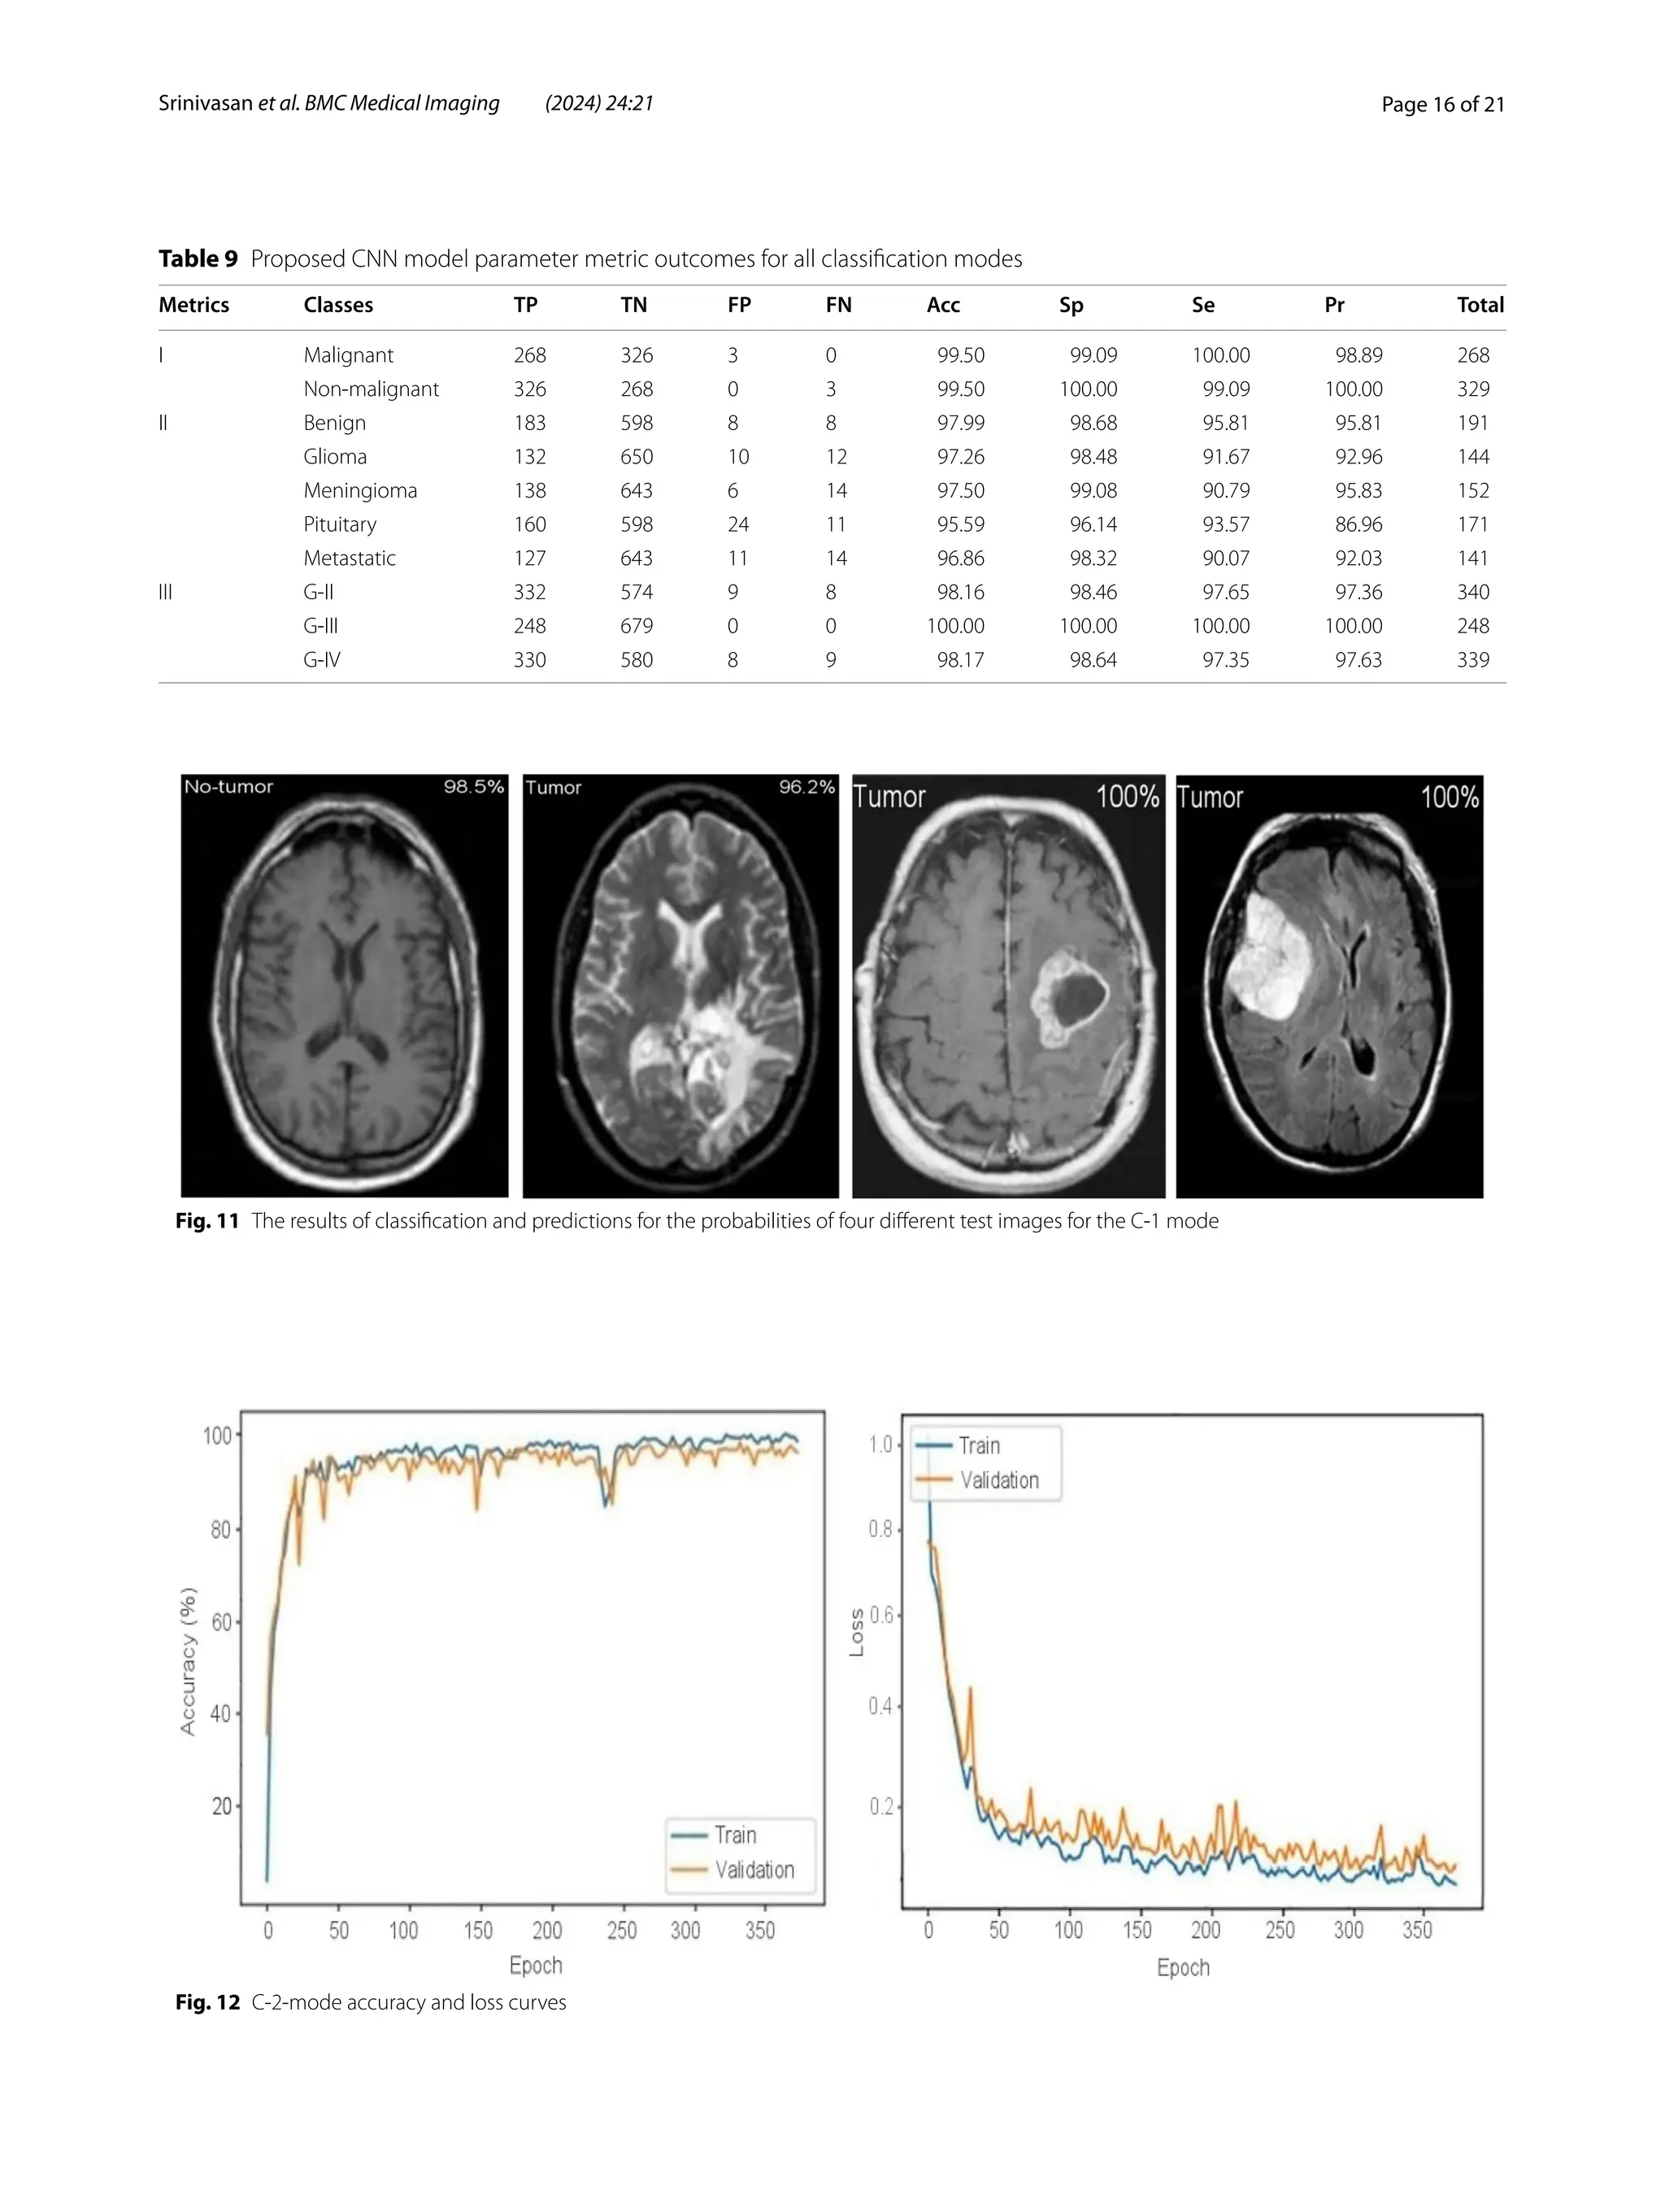

Table 9 Proposed CNN model parameter metric outcomes for all classification modes

Metrics Classes TP TN FP FN Acc Sp Se Pr Total

I Malignant 268 326 3 0 99.50 99.09 100.00 98.89 268

Non-malignant 326 268 0 3 99.50 100.00 99.09 100.00 329

II Benign 183 598 8 8 97.99 98.68 95.81 95.81 191

Glioma 132 650 10 12 97.26 98.48 91.67 92.96 144

Meningioma 138 643 6 14 97.50 99.08 90.79 95.83 152

Pituitary 160 598 24 11 95.59 96.14 93.57 86.96 171

Metastatic 127 643 11 14 96.86 98.32 90.07 92.03 141

III G-II 332 574 9 8 98.16 98.46 97.65 97.36 340

G-III 248 679 0 0 100.00 100.00 100.00 100.00 248

G-IV 330 580 8 9 98.17 98.64 97.35 97.63 339

identifying brain tumors. Table 9 shows the measures of

the accuracy, such as the true positive (TP), true negative

(TN), false positive (FP), false negative (FN), accuracy

(Acc), specificity (Sp), sensitivity (Se), and precision (Pr).

According to Table 9, an accuracy of 97.26% is attained

when classifying a glioma, 97.50% when classifying a

meningioma, 96.86% when classifying metastasis, 97.99%

when classifying a healthy brain, and 95.59% when clas-

sifying the pituitary tumor type for the C-2 mode.

fication-3 (C-3) task. Table 9 shows that an accuracy of

98.16% is reached when classifying grade II, 100% when

classifying grade III, and 98.17% when classifying grade